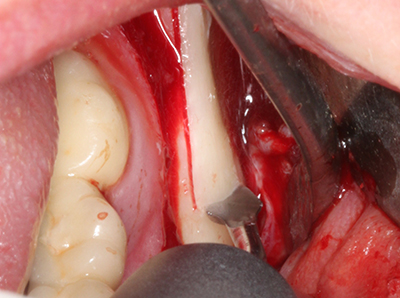

Fig. 18: Preparación de una tapa cortical con la sierra ósea piezoeléctrica (Piezomed, W&H).

Fig. 19: Zona operada después de neurolisis y eliminación del osteomo.

Fig. 20: La tapa ósea extraída se readapta y se fija mediante un tornillo para osteosíntesis (KLS Martin, Tuttlingen).